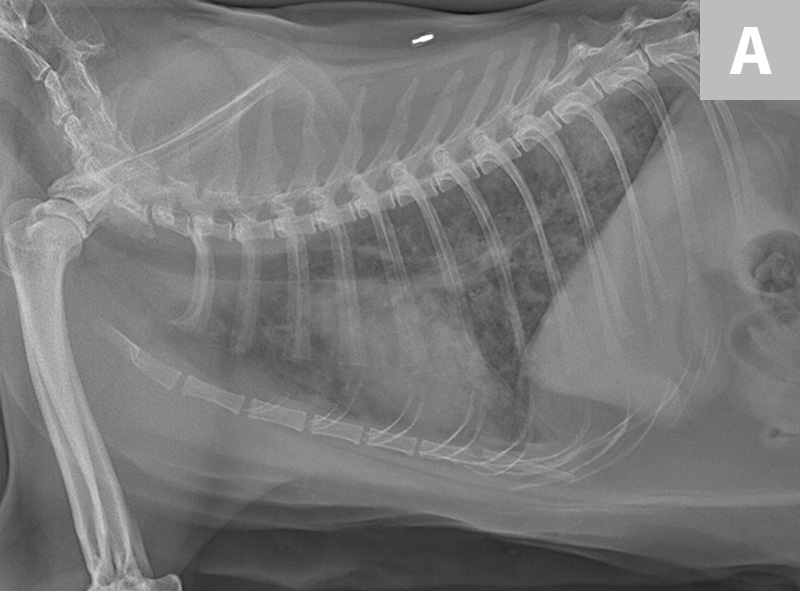

Sterile osteomyelitis in the ulnar diaphysis of a young indoor cat Osteomyelitis Cat Jaw Treatment Osteomyelitis is a serious and debilitating disease seen in cats. Bacterial osteomyelitis in veterinary patients can be challenging to diagnose and treat, given limited therapeutic options and. Cats can be susceptible to repeat episodes depending on the underlying cause. Courses of treatment are often lengthy and will require monitoring and regular checkups. A broad range of bacteria has been implicated. Osteomyelitis Cat Jaw Treatment.